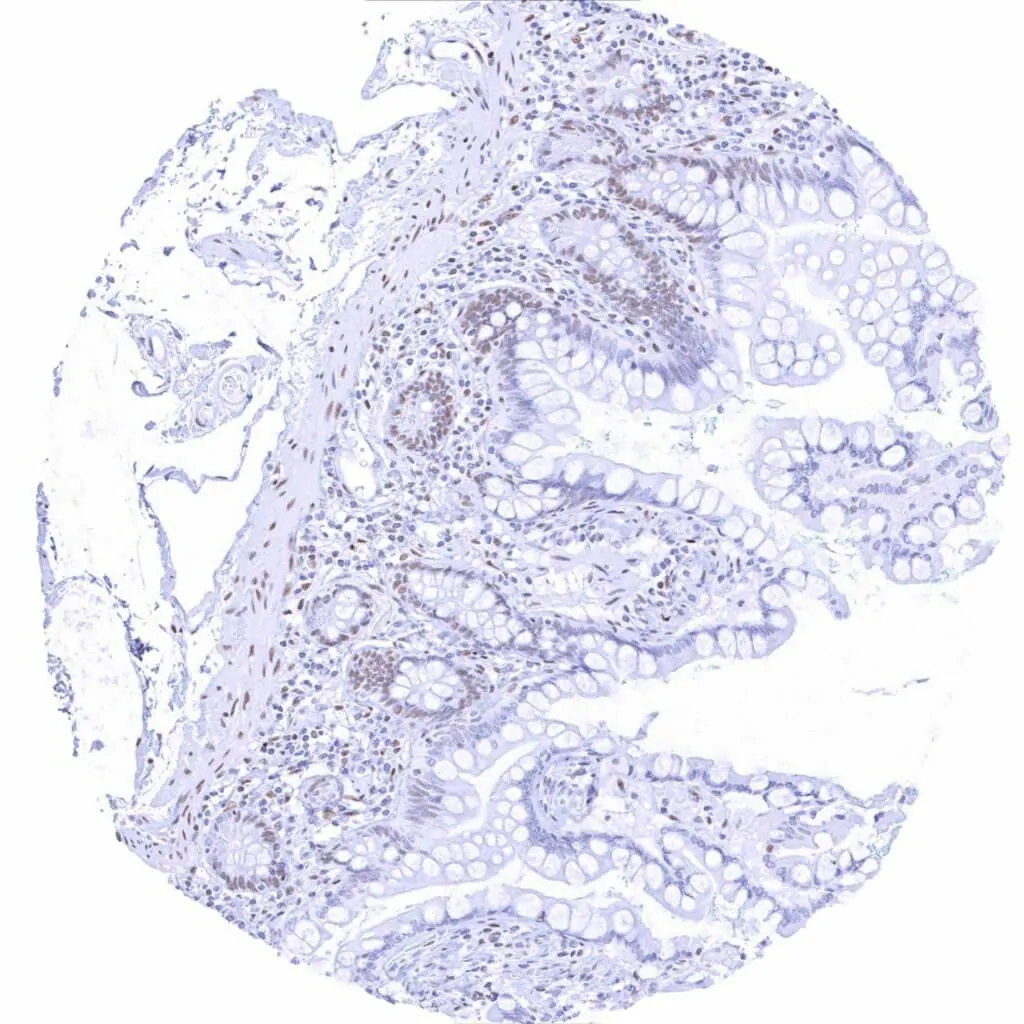

Appendix, mucosa – Weak to moderate TLE1 staining in epithelial cells. In this sample, staining is most intense at the surface and weaker in the crypts